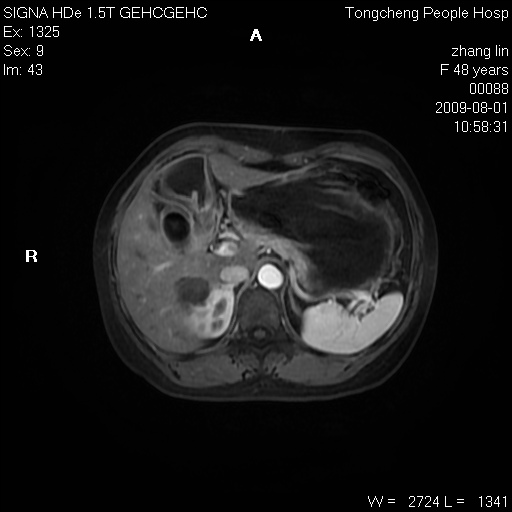

女,48岁。健康体检,彩超发现右肾占位性病变。平素健康。

临床诊断:右肾占位性病变,性质待定(囊肿?肿瘤?)。

上中腹部mr平扫+增强扫描,图像如下:

右肾上极见一类圆形病灶,t1wi呈等信号t2wi呈等高混杂信号,三期增强无强化,边界清---考虑囊肿出血。

同反相位均表现为等信号,病变无强化,考虑含蛋白的囊肿可能,弥散加权相或许有些帮助,

慢性胆囊炎